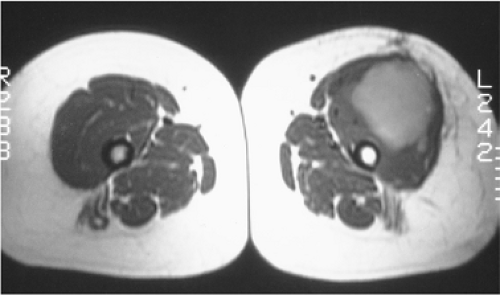

93e41b2c0cd00b407e9dbe829c33eb23.png

图-7戈谢病。MR显示双膝和脊柱骨髓内呈T1低信号。